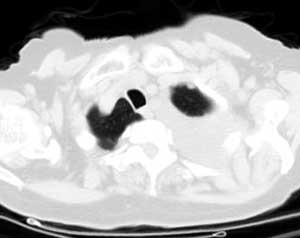

测ct值3-6hu,

既然ct值是3-6hu,还不如考虑包裹性积液。

从图片看,包裹性积液好象更合理,梭形,ct值3-5hu(在哪看到的?);胸膜间皮瘤如此规则,不多见。

左侧背部胸膜肥厚,伴包裹性积液,不考虑间皮瘤.

同意以上各位的高见,首先考虑包裹性积液,1.胸膜间皮瘤积液量一般较大,以游离性积液更为常见,2.可以看到增厚的胸膜结节